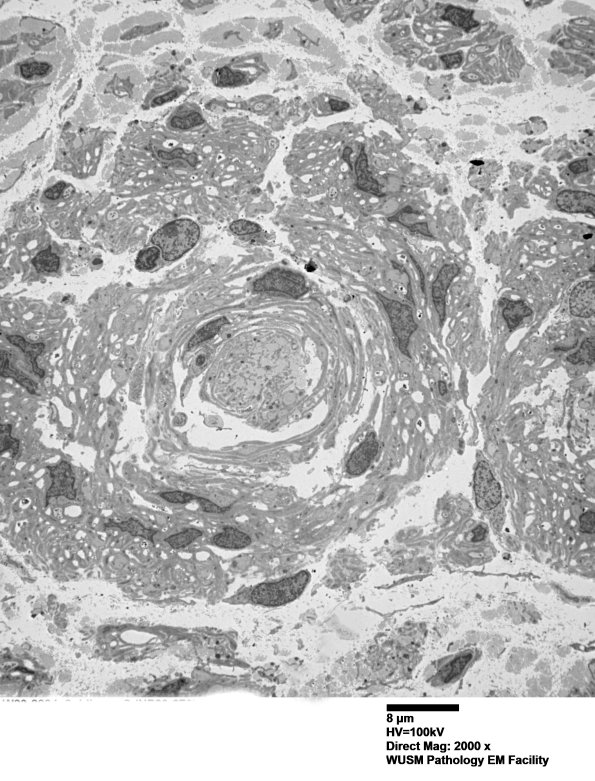

Washington University Experience | PERIPHERAL NEUROPATHY | 20 PSEUDO-ONION BULBS | 8C1A (Case 8) Nerve_010 - Copy

8C1A-E One large Schwannian aggregate is shown. A central structure is a large collection of collagen and Schwann cells with prominent basal laminae. The central process in this nerve is axon loss with numerous bands of Büngner and a very large "pseudo-onion bulb', representing a reaction to axonal degeneration and loss. There are no demyelinated axons, true onion-bulbs, macrophage-mediated demyelination, endoneurial macrophages with myelin debris, or ongoing axonal degeneration in our material. There are no regenerative axonal clusters. Unmyelinated axon loss is confirmed by large numbers of collagen pockets. (electron micrographs)